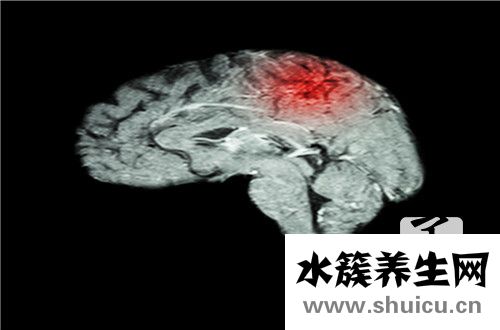

左側(cè)大腦內(nèi)徑標(biāo)準(zhǔn)值在1cm以下,是檢查嬰兒頭部是否有腦部疾病的一種方式,可以預(yù)防嬰兒先天性智力低下和腦積水的風(fēng)險(xiǎn)。但當(dāng)左側(cè)內(nèi)徑腦室超過(guò)1.5cm時(shí),一般寶寶都很?chē)?yán)重,這種寶寶不適合生育,要解決流產(chǎn)問(wèn)題。因此,孕婦在孕期應(yīng)采取良好的保障措施。

在中國(guó)醫(yī)療界廣泛認(rèn)為,胎寶寶的側(cè)腦室標(biāo)準(zhǔn)值應(yīng)該是在1cm下列的,假如在產(chǎn)檢的全過(guò)程中發(fā)覺(jué)胎寶寶側(cè)腦室稍大就務(wù)必高度重視起來(lái)。那哪些的狀況才算偏大呢?假如胎寶寶的側(cè)腦室做到了1cm到1.5cm中間,這一就算是輕度的腦部疾病了。假如胎寶寶的側(cè)腦室做到了1.5cm以上,那麼這一狀況針對(duì)胎寶寶而言就很?chē)?yán)重了。

這個(gè)時(shí)候胎寶寶便會(huì)有腦積水的風(fēng)險(xiǎn)性,可是在現(xiàn)實(shí)生活中有很多孕婦在產(chǎn)檢的全過(guò)程中發(fā)覺(jué)胎寶寶的側(cè)腦室會(huì)變寬十mm上下,可是生出來(lái)的小寶寶是身心健康的,因此需不需要再次開(kāi)展安胎醫(yī)治,要融合孕婦的人體標(biāo)準(zhǔn)和寶寶的別的生長(zhǎng)發(fā)育狀況。建議遵從本地醫(yī)師的建議,是再次懷孕還是終止懷孕。假如在做了查驗(yàn)以后發(fā)覺(jué)小寶寶的頭部有出現(xiàn)異常,業(yè)能夠 到上醫(yī)院門(mén)診開(kāi)展進(jìn)一步的定期檢查診斷,但假如上級(jí)領(lǐng)導(dǎo)醫(yī)院門(mén)診也建議開(kāi)展引產(chǎn)手術(shù),就需要充分準(zhǔn)備引產(chǎn)手術(shù)的手術(shù)治療的提前準(zhǔn)備了。由于診斷胎寶寶頭部有病癥還堅(jiān)持不懈生出來(lái),那樣對(duì)未來(lái)的小寶寶和自身全是一種壓力。

假如您的胎寶寶悲劇產(chǎn)生那樣的狀況。請(qǐng)一定要到上級(jí)領(lǐng)導(dǎo)醫(yī)院門(mén)診開(kāi)展進(jìn)一步的定期檢查診斷,不必為自己留有缺憾。另外在懷孕期間前幾個(gè)月需要留意自身的身心健康,不可以感染流感等病癥,要杜絕傳染性疾病等病癥源。假如您在懷孕初期遭到過(guò)感冒病毒的侵蝕,那麼您的胎寶寶身患腦部疾病的風(fēng)險(xiǎn)性可能擴(kuò)大。